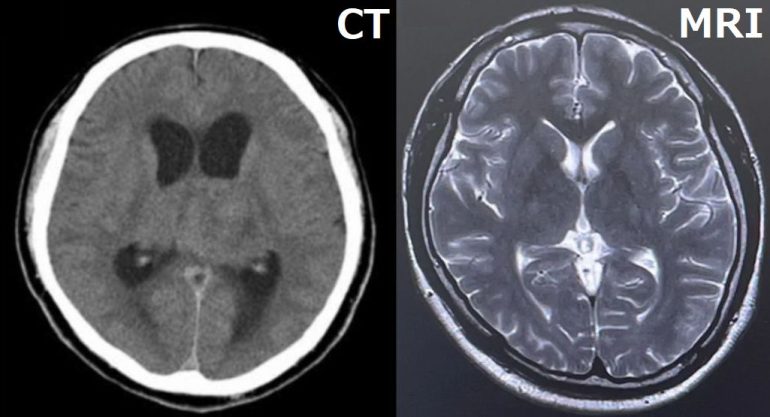

脳神経外科・脳神経内科クリニックへ行ってください。その際は必ずMRIかCTがある事を確認してください。特に脳神経内科の場合は設置がない場合があります。どんな名医でも頭の中を調べるにはMRIかCTによる検査が必須だからです。

Q.MRIとCTはどちらが良いですか?

推奨はMRIです。理由は血管撮影が容易な為、情報量が多く画質にも優れている為です。脳の撮影ならMRI優位が一般論です。

Q.どんなの病気が見つけられますか?

A.脳梗塞、脳出血、くも膜下出血、脳腫瘍、慢性硬膜下血腫など数多くの頭の病気を1度で確認出来ます。唯一、弱い部分は発症直後の脳出血ぐらいです。幅広い病気をカバーし、総合力で優れるのがMRIです。